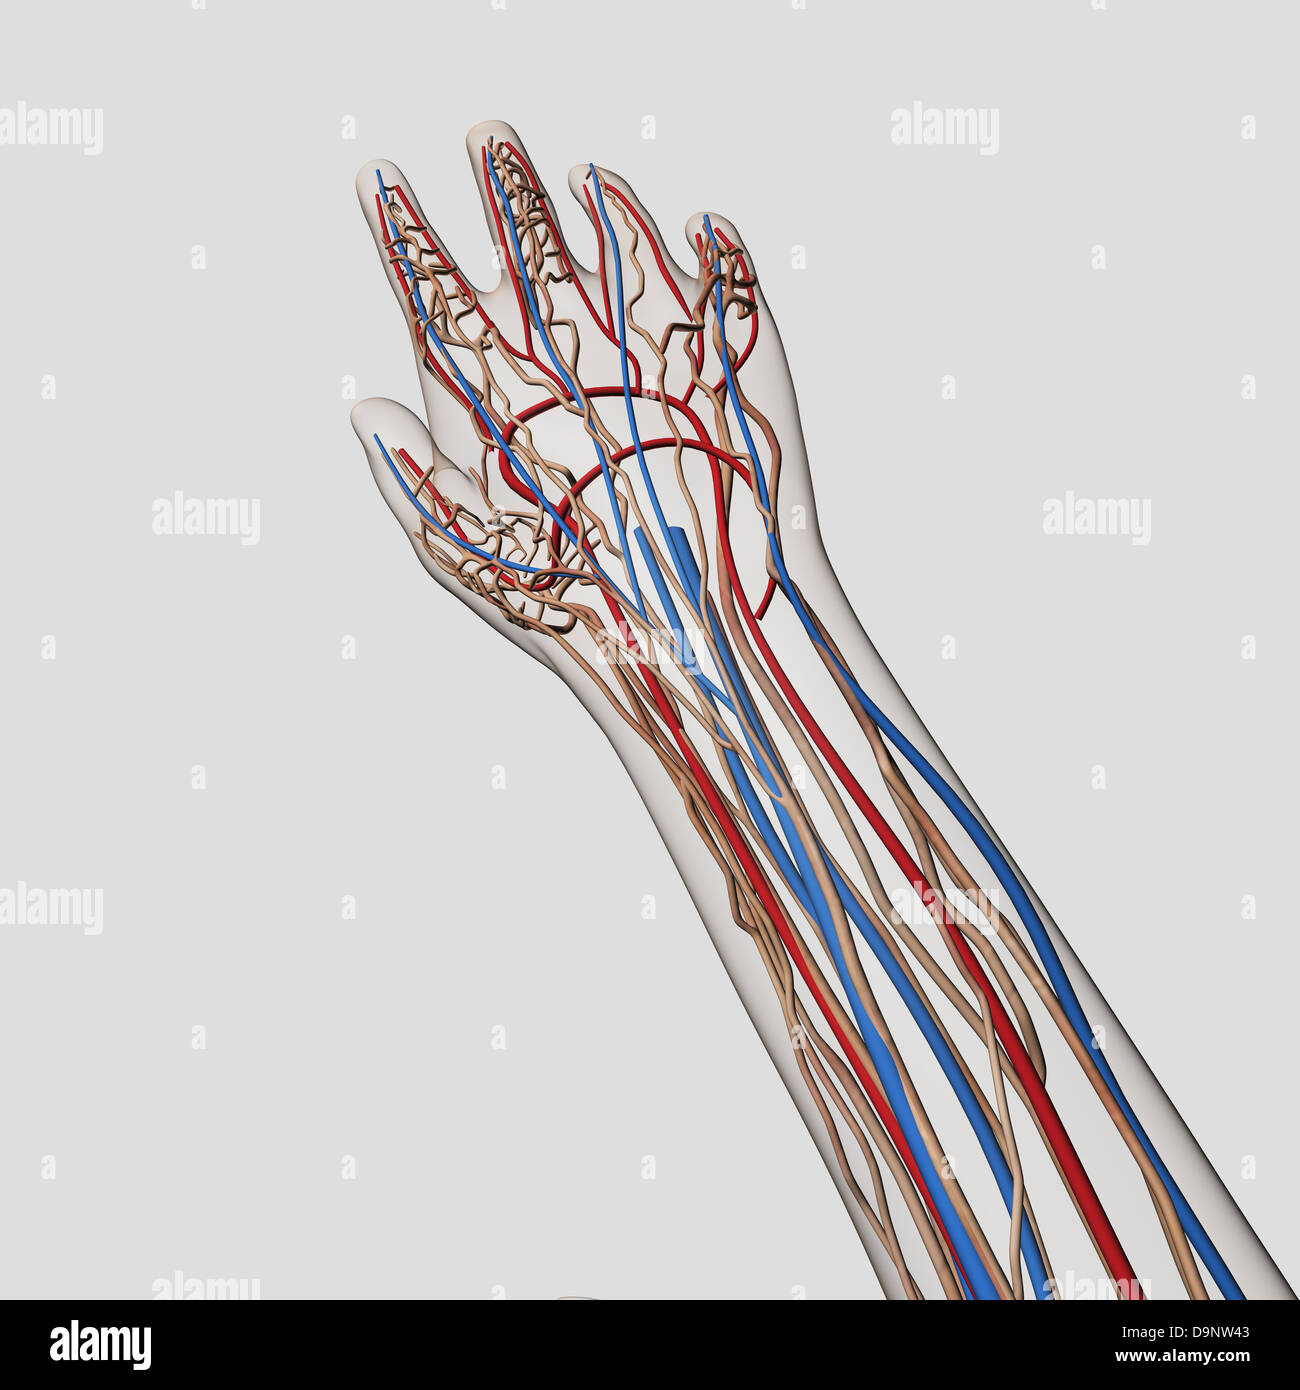

Medical illustration of arteries, veins and lymphatic system in human hand and arm. Stock Photohttps://www.alamy.com/image-license-details/?v=1https://www.alamy.com/stock-photo-medical-illustration-of-arteries-veins-and-lymphatic-system-in-human-57643715.html

Medical illustration of arteries, veins and lymphatic system in human hand and arm. Stock Photohttps://www.alamy.com/image-license-details/?v=1https://www.alamy.com/stock-photo-medical-illustration-of-arteries-veins-and-lymphatic-system-in-human-57643715.htmlRFD9NW43–Medical illustration of arteries, veins and lymphatic system in human hand and arm.